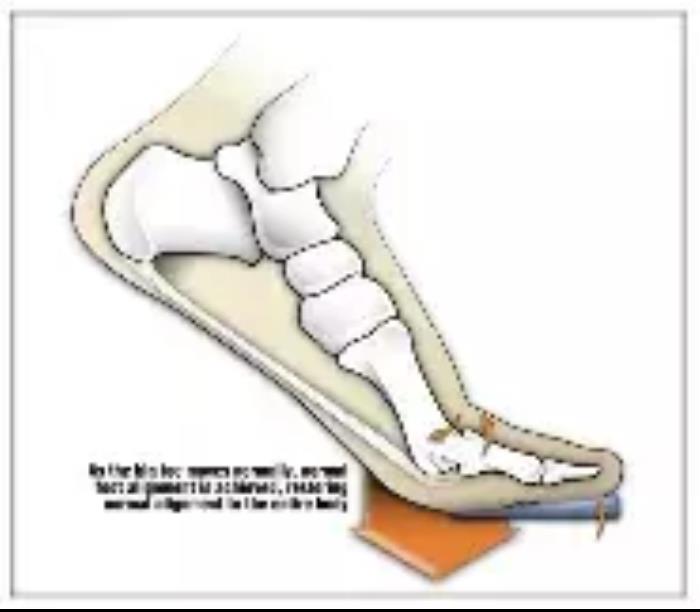

正确的思路应该是:考虑足弓的支撑,和前足的角度调整,从下肢生物力学出发矫正拇外翻。

配穿个人定制矫正鞋垫是个简单有效的解决方法。

配穿个人定制矫正鞋垫是个简单有效的解决方法。